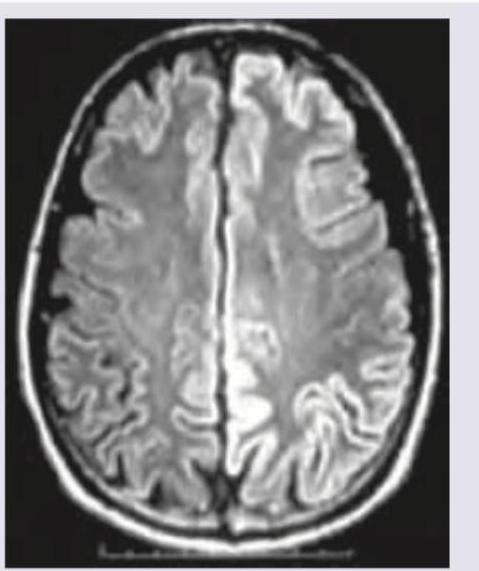

Question 2: MRI was performed on a 35-year-old man with progressive myoclonus and apathy. What is the diagnosis? (Recent NEET Pattern 2016-17)

Explanation: ***Prion disease*** - The MRI shows **cortical ribboning** (hyperintensity in the cortex) and possible signal changes in the basal ganglia, which are characteristic findings in prion diseases such as **Creutzfeldt-Jakob disease (CJD)**. - The clinical presentation of **progressive myoclonus** (sudden, involuntary muscle jerks) and **apathy** (lack of emotion or motivation), especially in a relatively young individual (35 years old), is highly suggestive of CJD or another prion disease. *Herpes simplex encephalitis* - This typically presents with **fever, headache, and focal neurological deficits**, often affecting the **temporal lobes**. - While it can cause FLAIR hyperintensities, it usually begins acutely with more prominent edema and may have hemorrhagic components, and myoclonus is not a primary defining symptom. *SSPE* - **Subacute sclerosing panencephalitis (SSPE)** is a rare, fatal, progressive brain disorder caused by the **measles virus**, primarily affecting children and young adults. - While it can cause progressive neurological deterioration and cognitive decline, myoclonus is often a late feature, and MRI findings often show **white matter demyelination** in later stages, which is not the predominant finding here. *Mesial temporal sclerosis* - This condition is characterized by **atrophy and signal changes in the hippocampus and amygdala** on MRI, typically associated with **temporal lobe epilepsy**. - While it can cause cognitive issues, it usually does not account for widespread cortical ribboning or prominent myoclonus in this age group, and the image does not specifically highlight mesial temporal lobe changes.